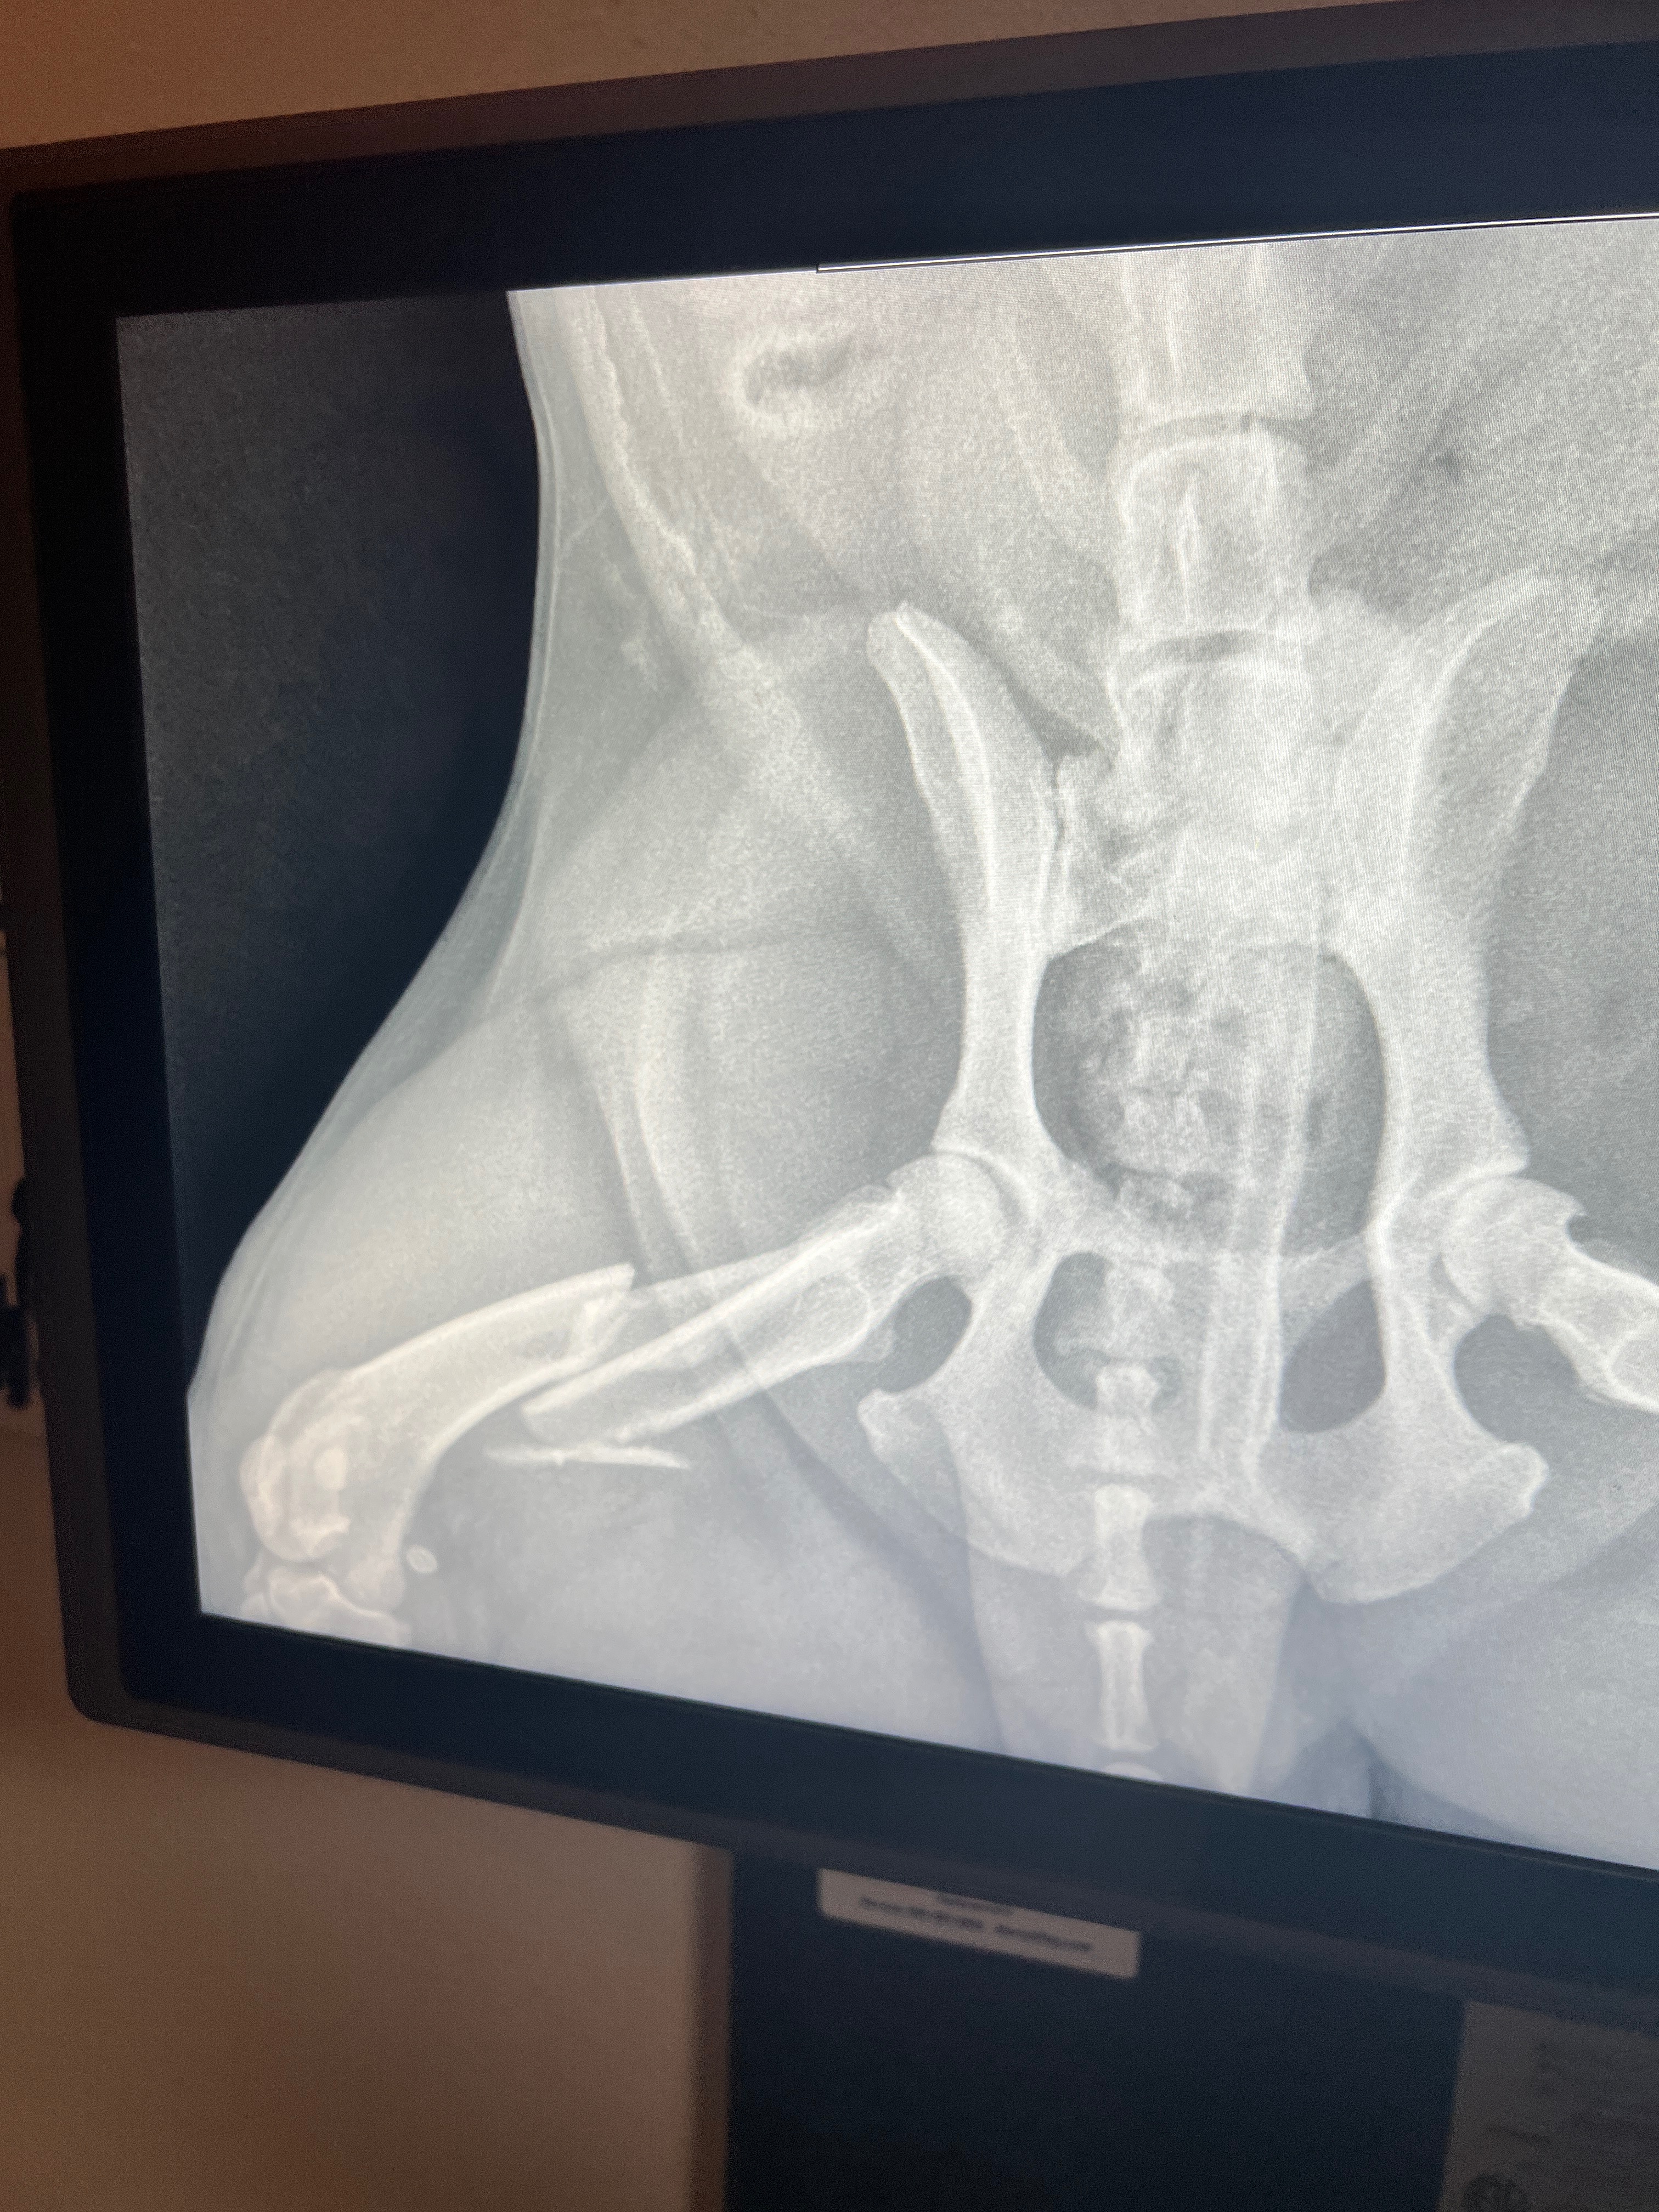

My name is Eric Pikyavit. I am raising funds for my dog (my baby dragon), Sitka Henry Pikyavit. He is nine years old and he has been by my side since he was a puppy. He is my best friend in this world and I can’t afford to help him. So I’m doing something I really don’t like to do… I’m asking for help, any help at all! He needs surgery. He jumped out of my car, and he broke his hip. I feel so bad and I know I shouldn’t blame myself, but I do because I know how he is when the window's down. He jumped out the window before, but he never rolled like he did this time. I heard a snap and saw him roll about six times. I slammed my brakes, put it in park, and he was already standing by the car with his leg in the air. I hugged him, asking him stupid questions as if he could answer me. I was going probably about 15 miles an hour around the corner.

I rushed him to the hospital in Cedar. They were able to take him in, but the doctor said the break is too complicated and I’m getting referred to St. George. I am not sure how much it’s going to cost; the doctor said it’s going to be in the thousands… So I’m hoping it doesn’t go over $3000.

This hits me hard, because when I was about ten years old, I had broken the same hip bone as Sitka’s. My right femur, and like his, the surgery was too complicated for Cedar City, I was transported to Salt Lake City. Because of how it broke and how young I was, Dr said I could never play football. So it was a major life change for me. I know his pain, I hate to know that my baby dragon is going through it. He is suffering until the surgery, which I hope is only about a week. He is a Pikyavit. He is strong. My hip broke back in the 90s and technology wasn’t at it’s best. They had to use weights to pull on my ankle to stretch my leg out, because of how it was broken, it was stretched over about a week. He will suffer but I know he will survive. I am asking and praying I get enough. I empathize, I sympathize and I’m a little traumatized. But we will prevail.